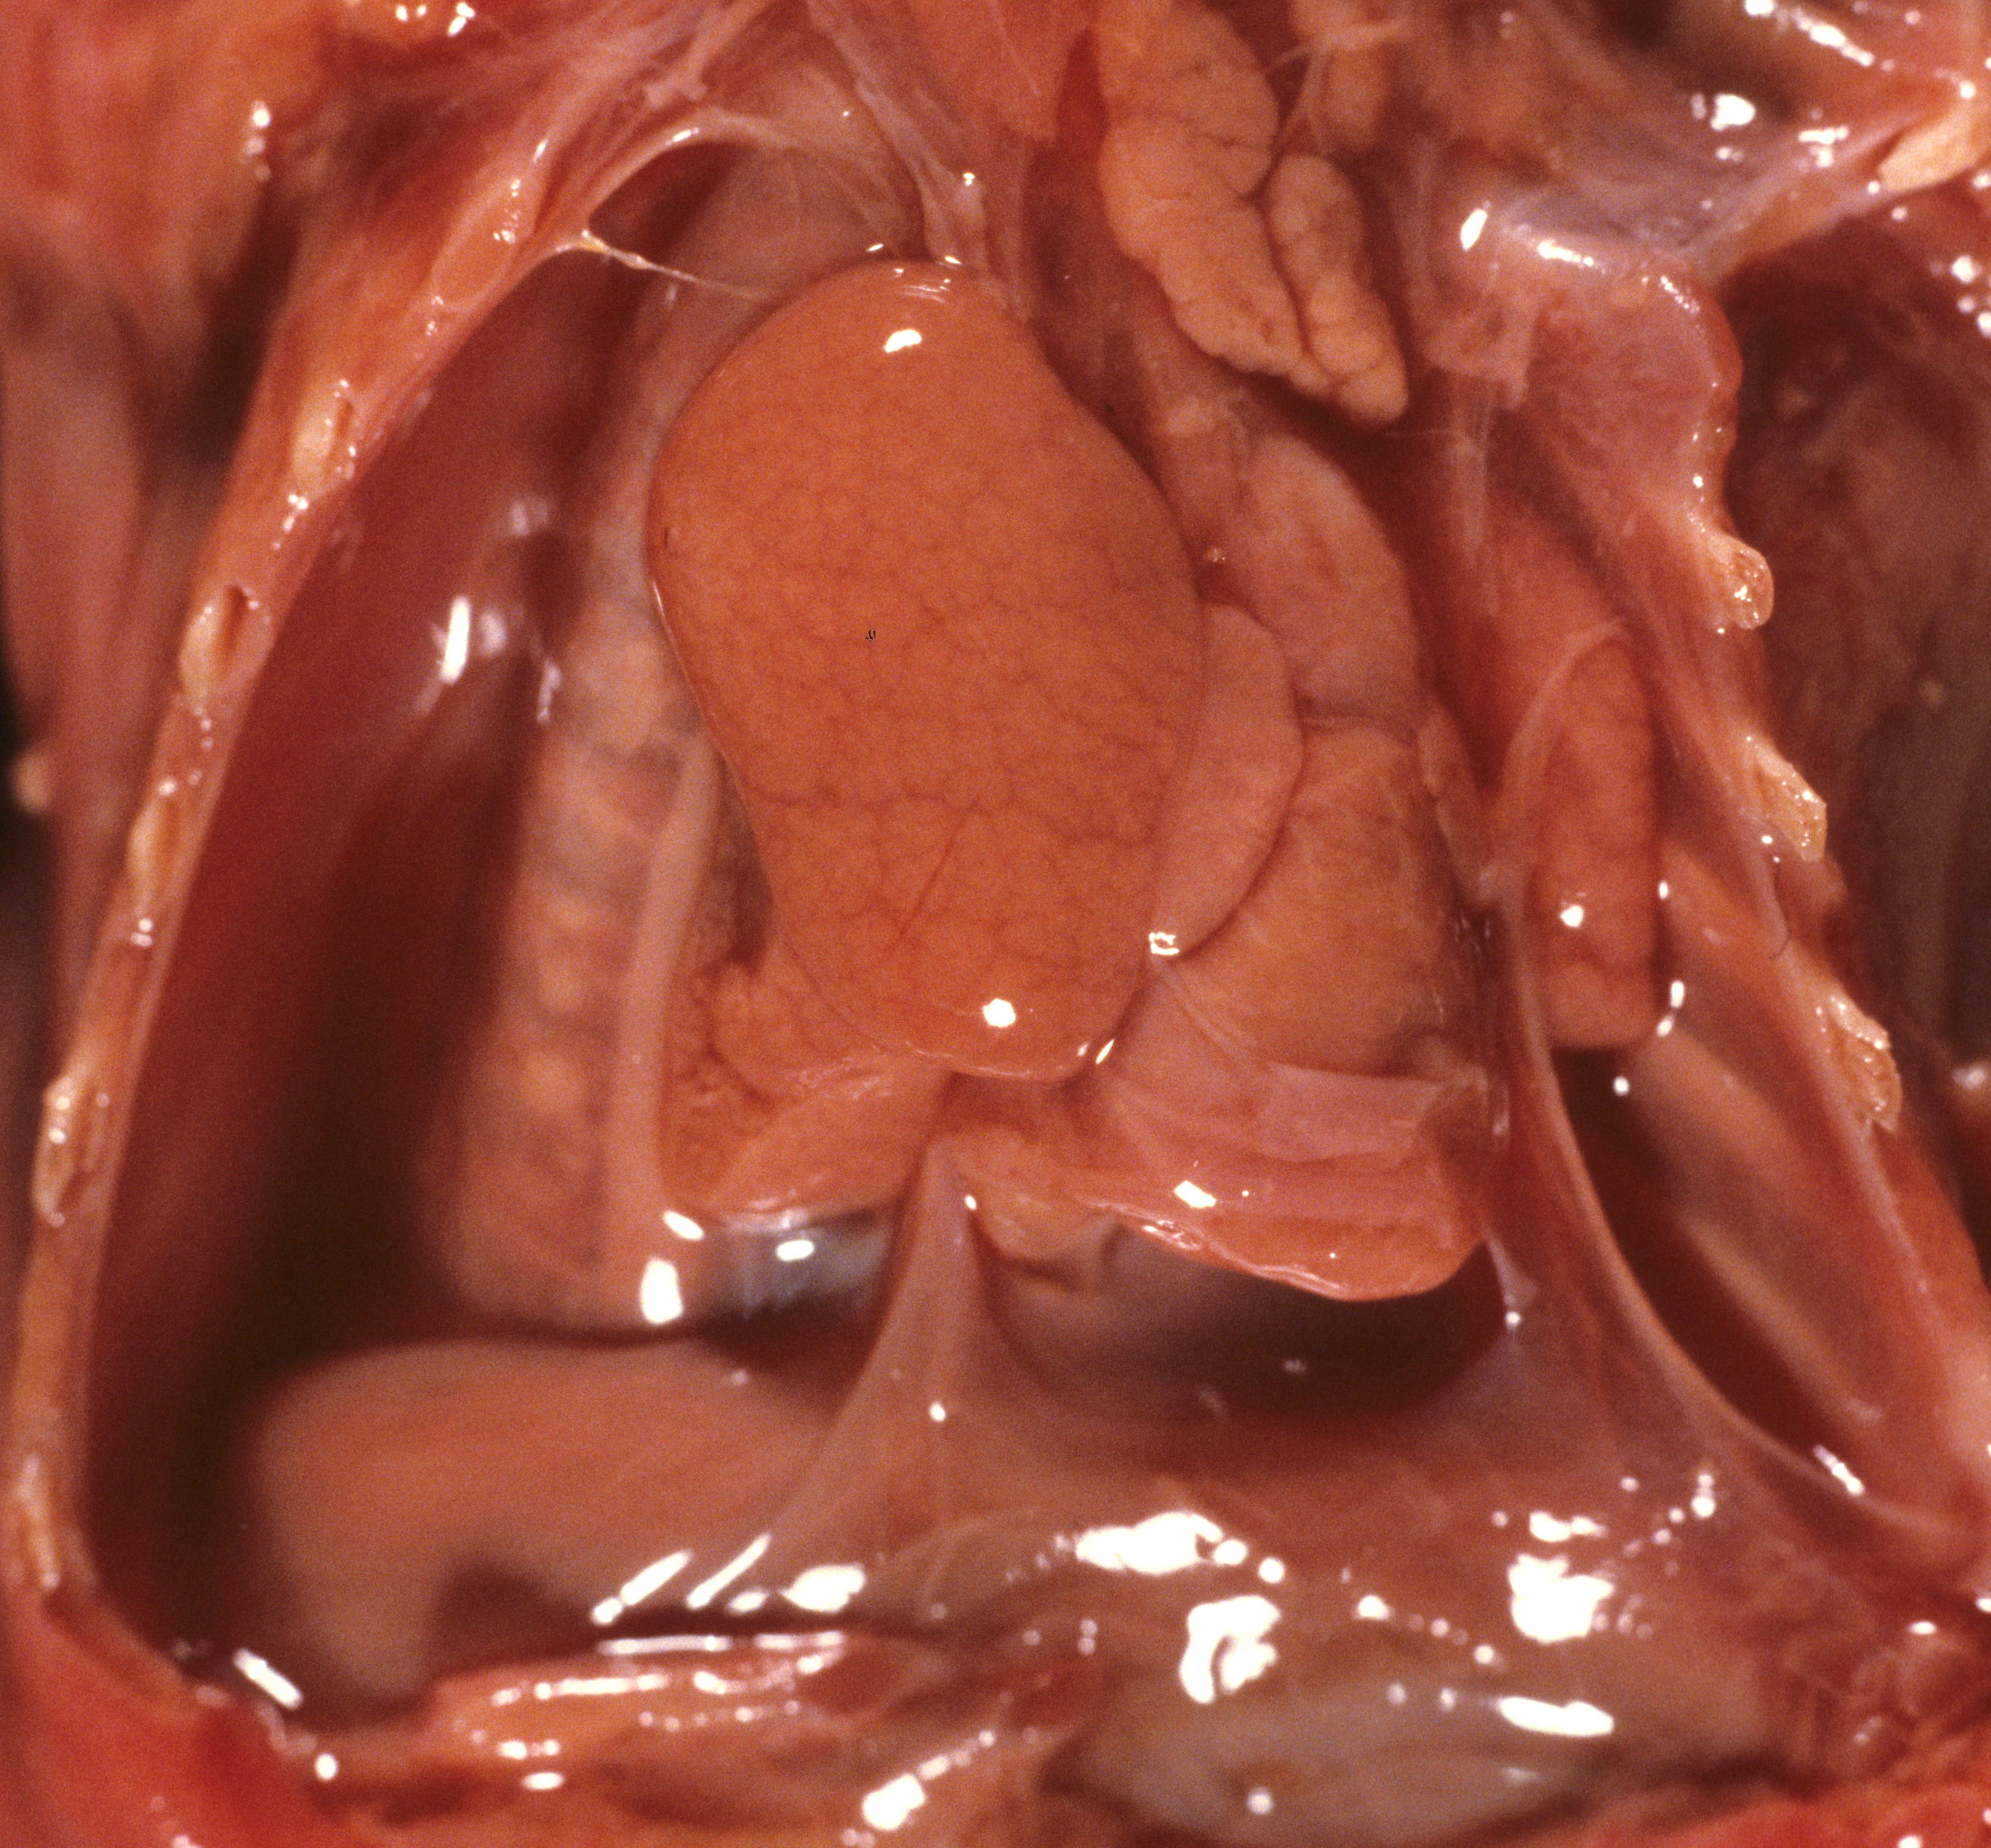

Pulmonary hypoplasia: Pulmonary hypoplasia may be apparent on opening the chest because the small lungs are obscured by the heart (Fig 1a,b).

The lung lobules should be identified noting three on the right and two lobes with a lingua on the left (Fig 2).